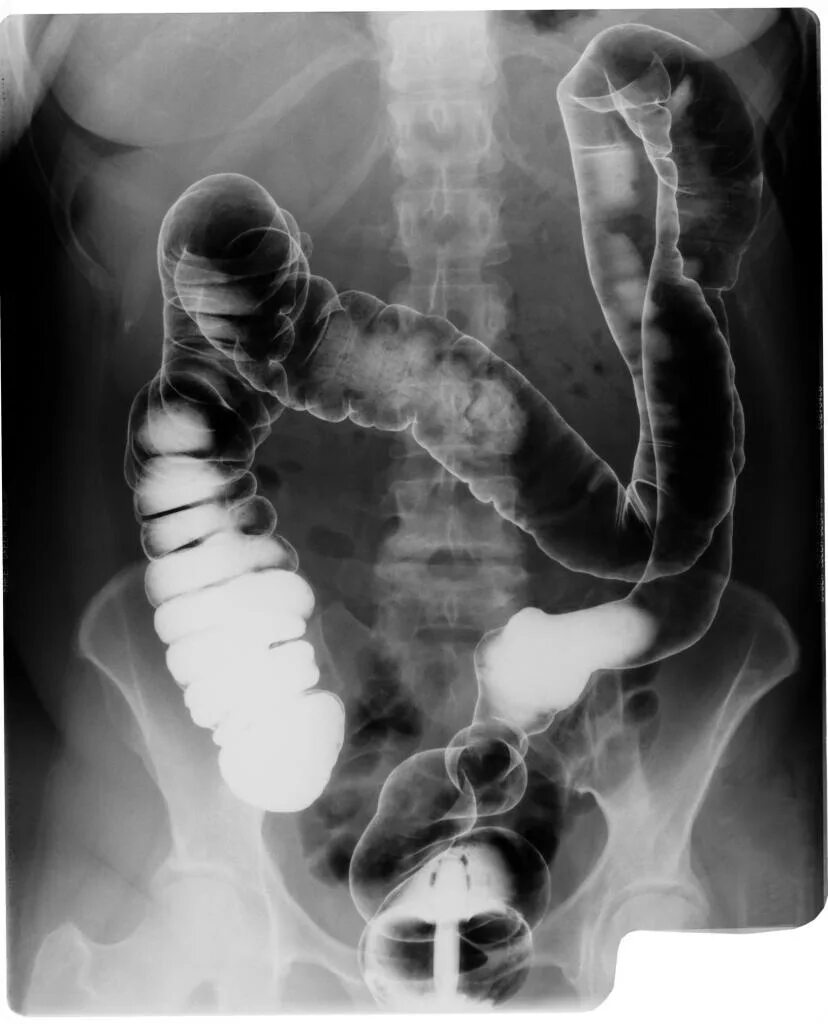

Кишечник после ирригоскопии